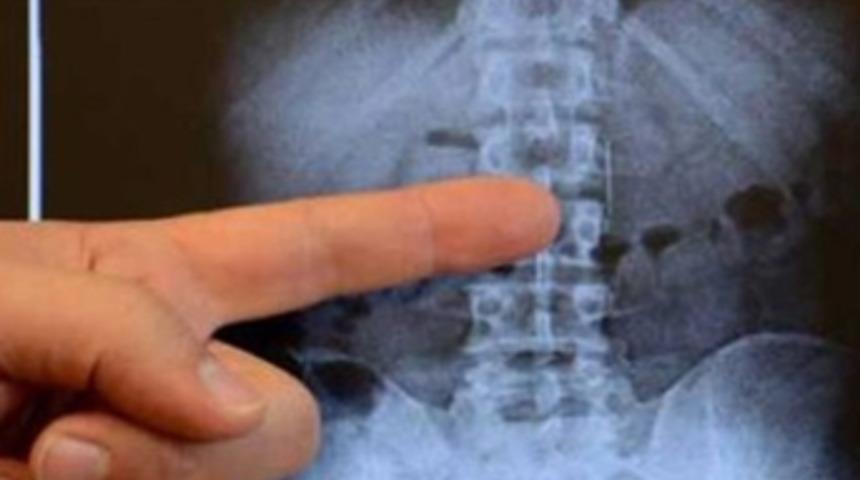

Erbay'ın onikiparmak bağırsağına saplanan iğne Genel Cerrahi uzmanı Opr. Dr. Bülent Erenoğlu, tarafından endoskopi yöntemiyle çıkartıldı.

Opr. Dr. Bülent Erenoğlu da yapılan tetkiklerde iğnenin onikiparmak bağırsağında enlemesine uzandığını ve her iki ucunun da bağırsağın duvarına saplandığını tespit ettiklerini kaydetti. Müdahale edilmeseydi iğnenin sağa ya da sola kayarak hayati damarlara ve safra yolunda yaralanmaya neden olabileceğine dikkat çeken Opr. Dr. Erenoğlu,